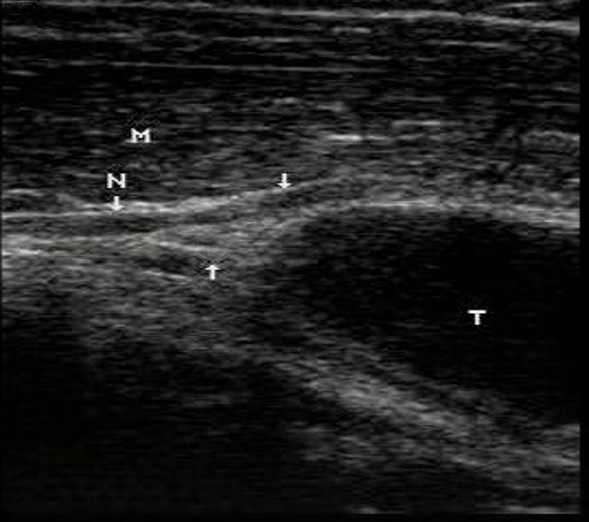

几种典型肌骨超声图片:

肘管综合征、尺神经卡压综合症:1、小指、环指的掌侧或者背侧麻木; 2、小指、环指的无力、感觉异常,偶尔可能掉东西。3、症状特点:最初为间断性,症状可呈持续性、进行性加重;打电话、开车或者用电脑时出现小指及环指麻木。